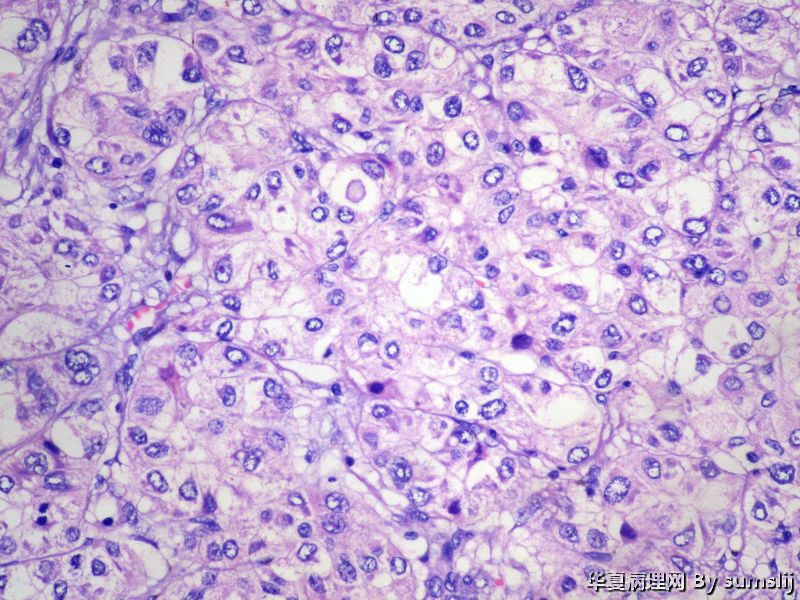

这是肝的混合性癌吗?

这是肝的混合性癌吗?图1

名称:图1

描述:IMG_2431

低分化肝细胞肝癌

肝细胞肝癌

肝细胞癌